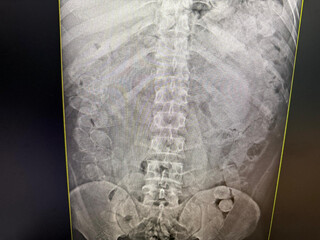

A equipe encaminhou os bolivianos para o Pronto-Socorro Municipal e o raio-X confirmou a ingestão das cápsulas. Eles ficaram na unidade sob escolta policial até conseguirem expelir a droga.